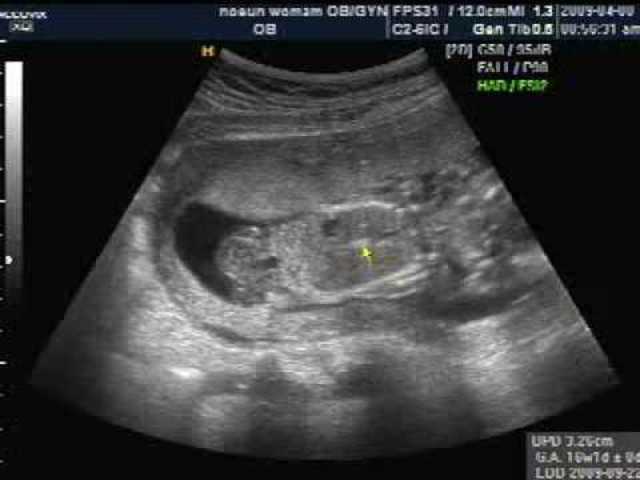

The baby is developing nostrils, mouth, lip, teeth buds, and eyelids. Fingers and toes are almost complete. All organs present, nut not mature yet. Affect on mother, the breasts become firmer and fuller and may ache. Fatigue, nausea, and frequent urination may still occur.

-

The baby can suck its thumb, swallow, hiccup, aand move around. Facial features become more clear. Affects on the mother, the abdomen continues to grow slower, morning sickness is usually gone. Appetite increases